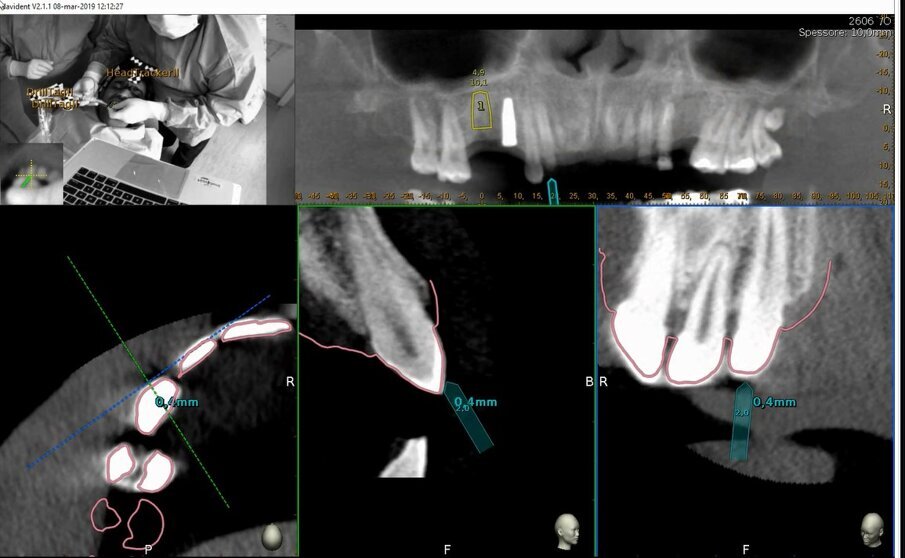

Il paziente R.V. di anni 40 affetto da Neurofibromatosi di tipo I, non fumatore e con neurofibroma palatino è reduce da intervento di avulsione dell’elemento 2.6 e cistectomia con concomitante socket preservation a cielo coperto ed inserimento sempre contestuale di impianto 2.5 in tecnica navigata; necessita per il completamento della riabilitazione dell’emiarcata superiore sinistra dell’inserimento di un secondo impianto in zona 2.6 (Figg. 1a, 1b). La ceratura diagnostica digitale evidenzia, già nel primo intervento, un importante compromesso estetico- igienico accettato dal paziente in virtù della firbomatosi da cui è affetto che ha scoraggiato qualsiasi procedura invasiva (un’esperienza personale nel trattamento del padre riporta un sanguimento difficilmente controllabile della mucosa affetta in corso di chirurgia a cielo aperto ed una guarigione dei tessuti particolarmente imprevedibile anche quando cheratinizzati; nulla è stato trovato al riguardo in letteratura). (Fig. 2).

Figg. 1a, 1b - Situazione iniziale.